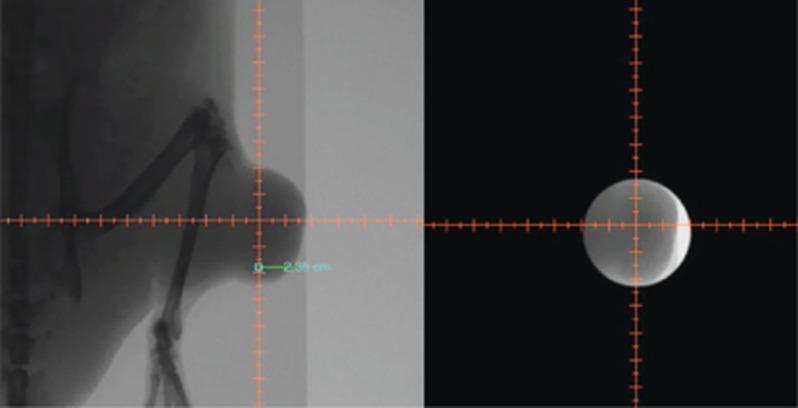

Dunning R3327-AT1 prostate tumours were evaluated by DCE MRI following intravenous injection of Gd-DTPA. The next day tumours were irradiated (single dose of 30 Gy), while animals breathed air (n=4) or oxygen (n=4); two animals were non-irradiated controls. Growth was followed and tumour volume-quadrupling time (T4) was compared with pre-irradiation DCE assessments.

Irradiation caused significant tumour growth delay (T4 ranged from 28 to 48 days for air-breathing rats, and 40 to 75 days for oxygen-breathing rats) compared with the controls (T4=7 to 9 days). A strong correlation was observed between T4 and extravascular-extracellular volume fraction (ve) irrespective of the gas inhaled during irradiation. There was also a correlation between T4 and volume transfer constant (K(trans)) for the air-breathing group alone.